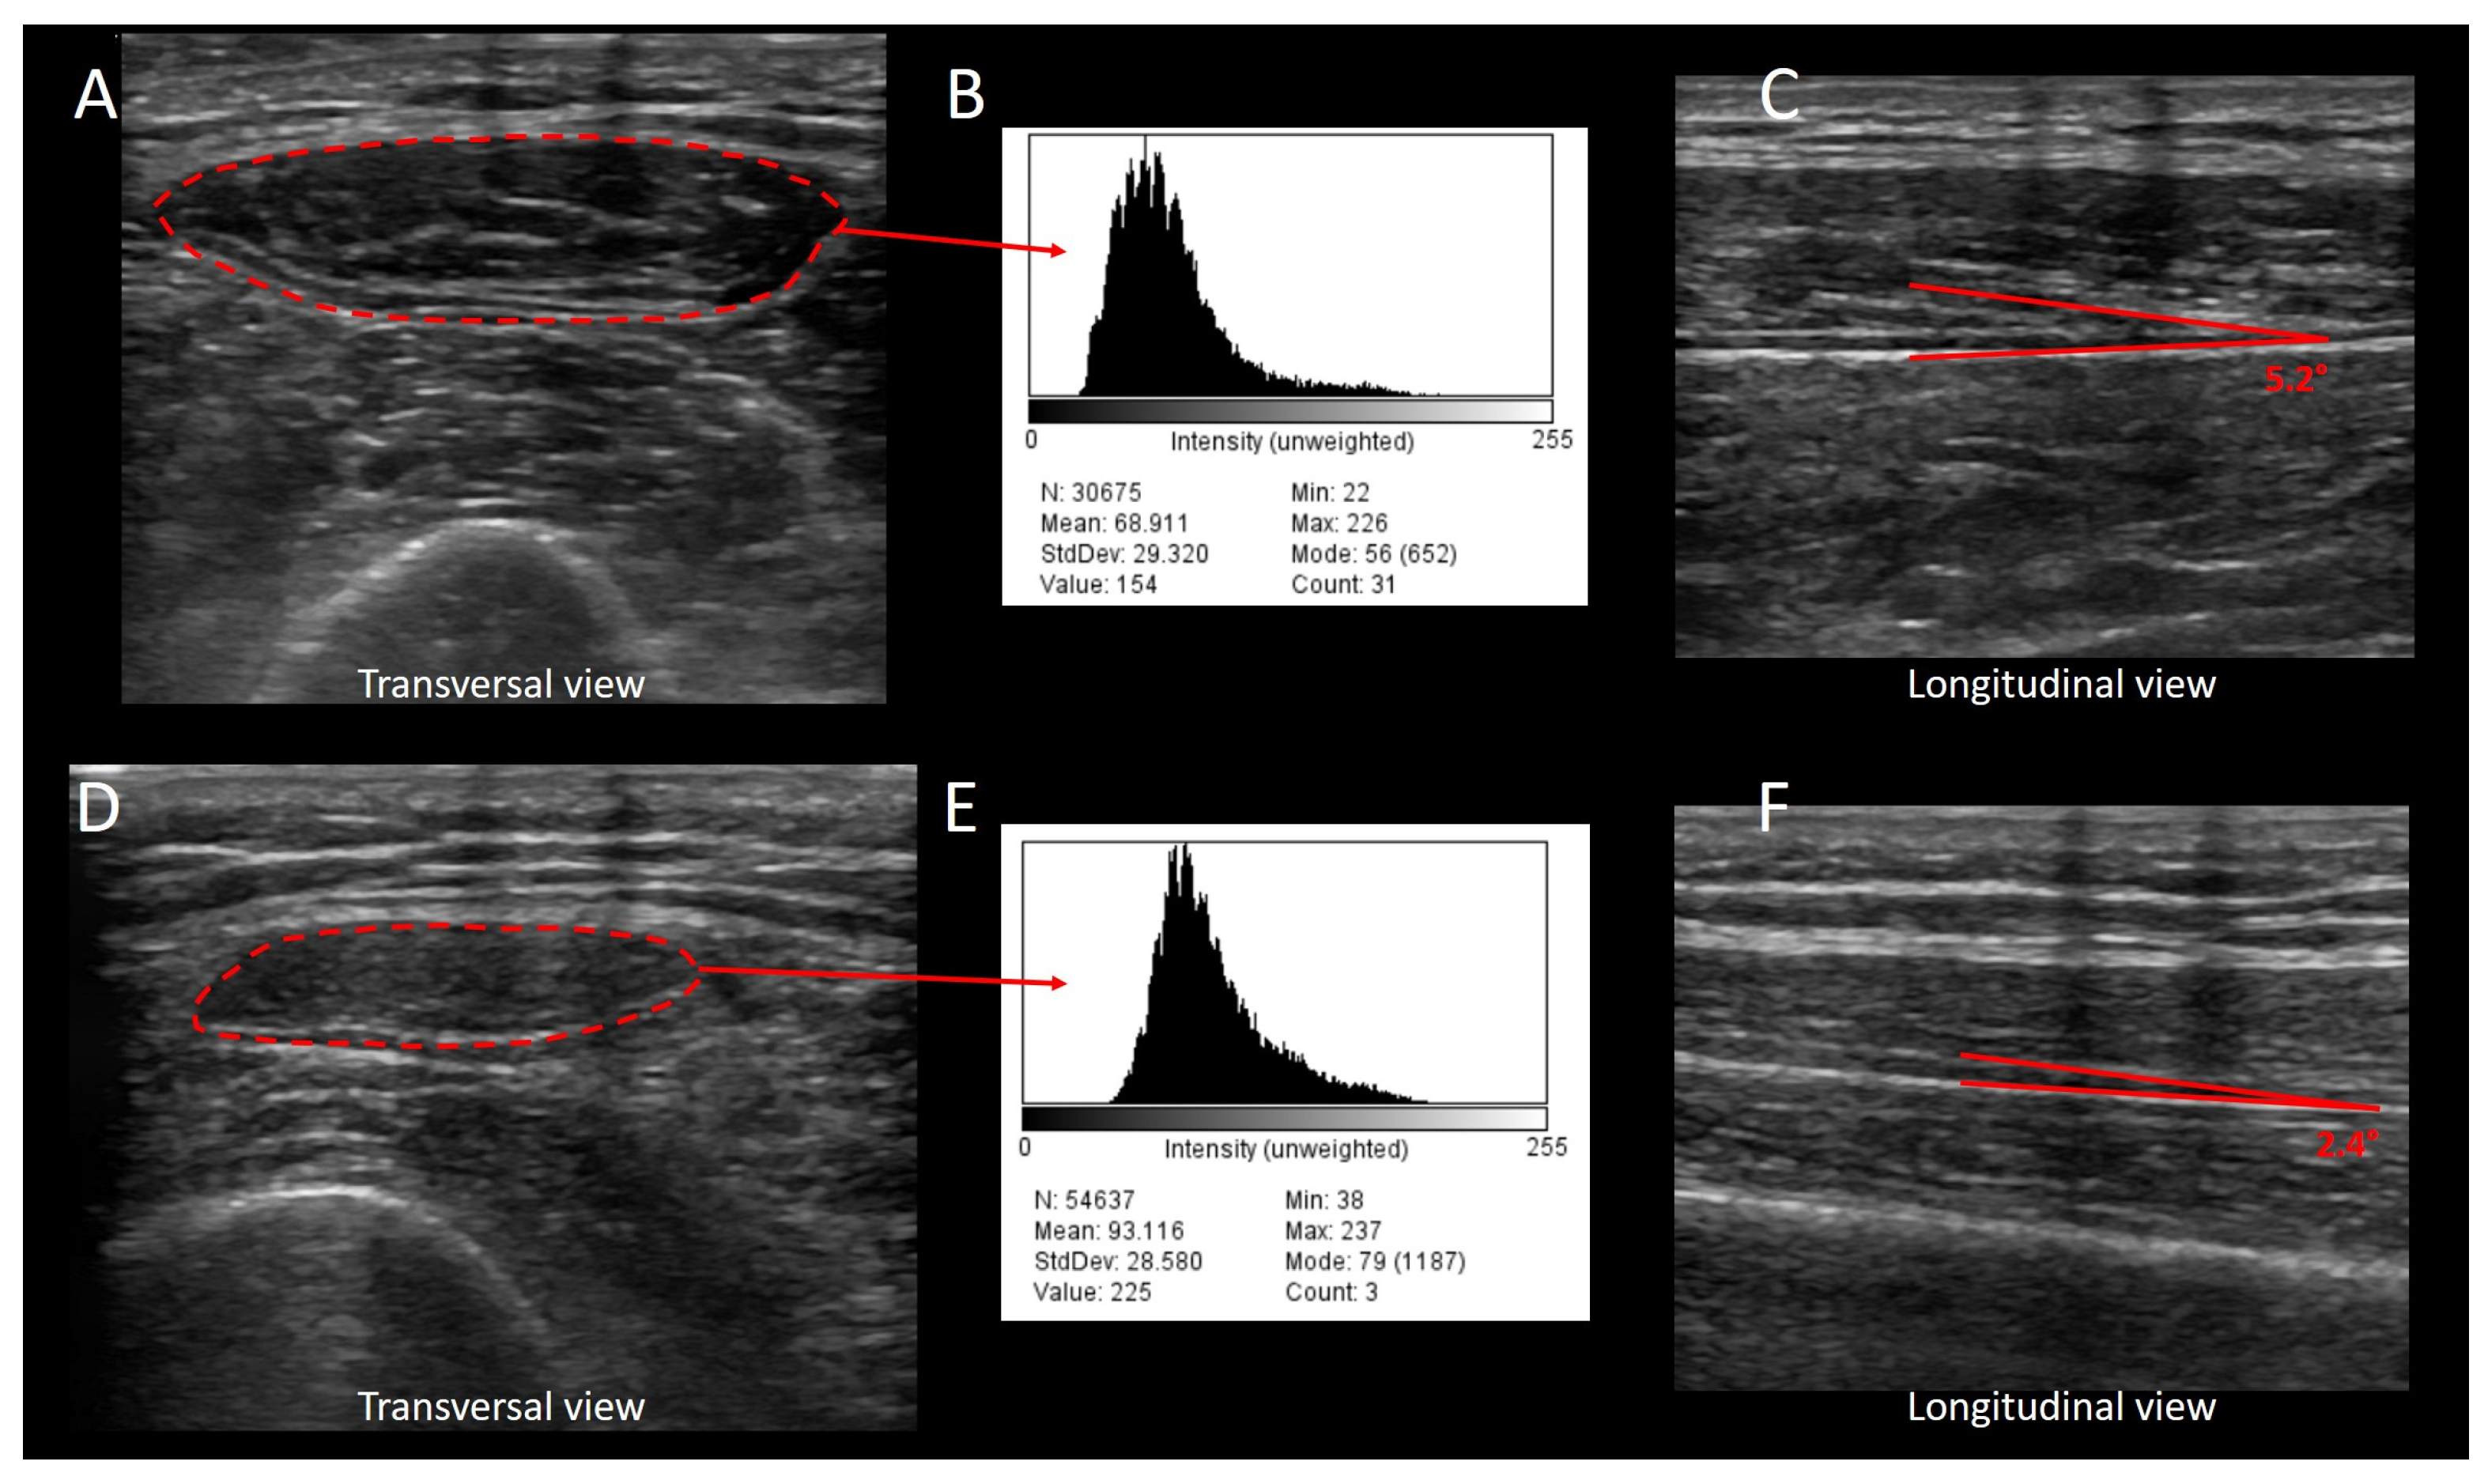

- Albayda, J.; van Alfen, N. Diagnostic Value of Muscle Ultrasound for Myopathies and Myositis. Curr. Rheumatol. Rep. 2020, 22, 82. [Google Scholar] [CrossRef]

- Pillen, S.; van Keimpema, M.; Nievelstein, R.A.; Verrips, A.; van Kruijsbergen-Raijmann, W.; Zwarts, M.J. Skeletal muscle ultrasonography: Visual versus quantitative evaluation. Ultrasound Med. Biol. 2006, 32, 1315–1321. [Google Scholar] [CrossRef]

- Schneider, C.A.; Rasband, W.S.; Eliceiri, K.W. NIH Image to ImageJ: 25 years of image analysis. Nat. Methods 2012, 9, 671–675. [Google Scholar] [CrossRef] [PubMed]

- Harris-Love, M.O.; Seamon, B.A.; Teixeira, C.; Ismail, C. Ultrasound estimates of muscle quality in older adults: Reliability and comparison of Photoshop and ImageJ for the grayscale analysis of muscle echogenicity. PeerJ 2016, 4, e1721. [Google Scholar] [CrossRef] [PubMed]

- Crawford, S.K.; Lee, K.S.; Bashford, G.R.; Heiderscheit, B.C. Spatial-frequency Analysis of the Anatomical Differences in Hamstring Muscles. Ultrason. Imaging 2021, 43, 100–108. [Google Scholar] [CrossRef] [PubMed]

- Puthucheary, Z.A.; Phadke, R.; Rawal, J.; McPhail, M.J.W.; Sidhu, P.S.; Rowlerson, A.; Moxham, J.; Harridge, S.; Hart, N.; Montgomery, H.E. Qualitative Ultrasound in Acute Critical Illness Muscle Wasting. Crit. Care Med. 2015, 43, 1603–1611. [Google Scholar] [CrossRef]